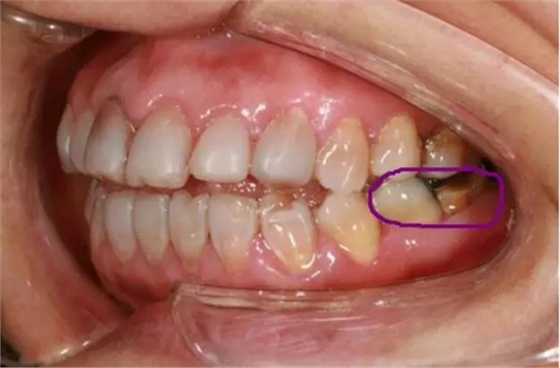

5,粉色線牙齒缺損(圖二)

美學(xué)修復(fù)不單是指擋擋門面,同時(shí)我們應(yīng)恢復(fù)患者正常的生理頜位及咬合關(guān)系,在滿足美觀的同時(shí)恢復(fù)患者的咀嚼功能。

(圖二)